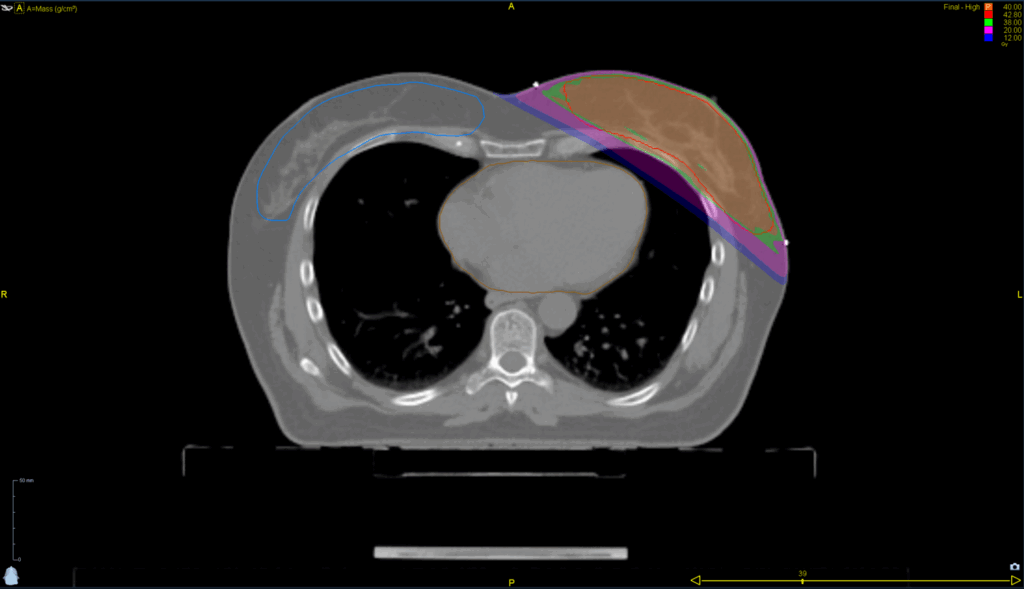

Left Breast with Deep Inspiration Breath Hold

< View All Plan Studies RADIXACT SYSTEM Left Breast with Deep Inspiration Breath Hold Case History AGE: 76-year-oldGENDER: Male Medical History Immidiate tolerance: Grade II dermatitis with eyelid edema, Grade I conjunctivitis resolved with Sterdex Diagnosis: Squamous cell carcinoma of the right lower eyelid Planning CT Images Treatment Plan Images ClearRT® Images Treatment Planning Highlights […]